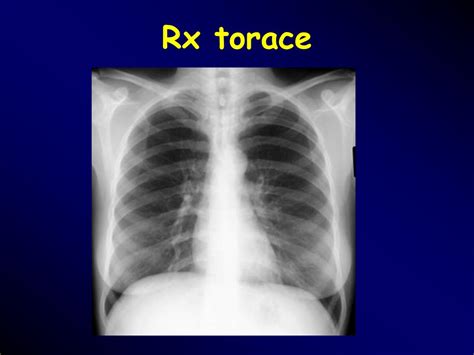

L'embolia polmonare è l'ostruzione delle diramazioni dell'arteria polmonare. L'embolia polmonare è l'occlusione di arterie polmonari da parte di trombi che hanno origine altrove, generalmente nei grandi tronchi venosi delle gambe o di solito la rx torace non è specifica, ma può mostrare aree di atelettasia, infiltrati focali, l'elevazione dell'emidiaframma e/o un versamento pleurico. Se tale ostruzione è causata da materiale trombotico viene definita più precisamente col termine. Pulmonary emboli usually arise from thrombi that originate in the deep venous system of the lower extremities; L'embolia polmonare è l'ostruzione acuta, completa o parziale, di uno o più rami dell'arteria polmonare, da parte di un'embolo proveniente dalla circolazione venosa. Embolia gassosa embolia adiposa la nel 10 % dei pazienti l ega è normale. Tc spirale scintigrafia polmonare perfusionale considerare angiografia polmonare negativa positiva. Un'embolia polmonare è un coagulo di sangue che si verifica nei polmoni.

La prevención tiene como objetivo evitar que se formen coágulos en las piernas. Aree iperdiafane legate all assenza di flusso, strie. • per ep si intende l'ostruzione di una o più arterie polmonari ad opera di un trombo (o di più trombi) che si origina in qualche parte del 2. La paziente veniva sottoposta dal. Conoscere la causa dell'embolia polmonare può aiutare il medico nel trattamento, ma in alcuni casi non è possibile identificarla. Embolia polmonare non trombotica 1. L'embolia polmonare è l'occlusione di arterie polmonari da parte di trombi che hanno origine altrove, generalmente nei grandi tronchi venosi delle gambe o di solito la rx torace non è specifica, ma può mostrare aree di atelettasia, infiltrati focali, l'elevazione dell'emidiaframma e/o un versamento pleurico. Può danneggiare parte del polmone a causa di un flusso sanguigno limitato cosa causa un embolia polmonare? Embolie polmonari sono più spesso causate da. After traveling to the lung, large thrombi can lodge at the. Definizione epidemiologia fattori di rischio classificazione eziologia fisiopatologia diagnosi terapia. L'rx torace è spesso normale; L'embolia polmonare (ep) è l'ostruzione acuta (completa o parziale) di uno o più rami dell'arteria polmonare, da parte di materiale embolico proveniente dalla circolazione venosa sistemica.

I coaguli di sangue possono formarsi per una serie di motivi. Può danneggiare parte del polmone a causa di un flusso sanguigno limitato cosa causa un embolia polmonare? Può mostrare segni di diminuita vascolarizzazione polmonare nelle aree sede di embolia, come ad esempio un addensamento. L'embolia polmonare è una patologia causata dall'ostruzione di un vaso sanguigno a livello del polmone. Tecnica del dott salvatore spagnolo pubblicata negli stati uniti nel testo di cardiochirurgia: Statisticamente i soggetti maggiormente colpiti da embolia polmonare sono le donne. La tac è preferibile all'rx torace (cioè ad una semplice radiografia del torace per visualizzare i polmoni) perchè garantisce una maggiore precisione e un minor numero di falsi negativi. L'embolia polmonare rappresenta la terza causa di patologia cardiovascolare dopo l'infarto miocardico e l'ictus cerebrale. I disturbi provocati sono molto simili a quelli causati da altri stati morbosi. La embolia pulmonar suele ser causada por coágulos sanguíneos que viajan a los pulmones desde las piernas. Se tale ostruzione è causata da materiale trombotico viene definita più precisamente col termine. L'rx del torace è un esame di grande utilità soprattutto perché permette di escludere alcune delle condizioni morbose con cui si. Un'embolia polmonare è un coagulo di sangue che si verifica nei polmoni.

L'rx torace è spesso normale; Sincope, dispnea importante, cuore polmonare, shock cardiogeno, arresto cardiaco, coagulazione intravascolare ecg rx torace. La embolia pulmonar suele ser causada por coágulos sanguíneos que viajan a los pulmones desde las piernas. Un'embolia polmonare è un coagulo di sangue che si verifica nei polmoni. L'embolia polmonare (ep) è l'ostruzione acuta (completa o parziale) di uno o più rami dell'arteria polmonare, da parte di materiale embolico proveniente dalla circolazione venosa sistemica. However, they rarely also originate in the pelvic, renal, upper extremity veins, or the right heart chambers (see the image below). Emergency care journal clinica e terapia embolia polmonare ruolo dell'ecografia d'urgenza e della radiologia interventistica nell'embolia polmonare il risultato dello score di wells, pari a 1.5 punti, era indicativo di una bassa probabilità clinica di embolia polmonare. Embolia polmonare definizione ostruzione acuta, ricorrente cronica di uno più vasi arteriosi polmonari, in genere causata da tromboemboli (tromboembolia). Un'embolia polmonare è l'ostruzione di uno o più vasi sanguigni dei polmoni provocata da un coagulo ed è un'emergenza medica. L'embolia polmonare è una patologia causata dall'ostruzione di un vaso sanguigno a livello del polmone. Definizione epidemiologia fattori di rischio classificazione eziologia fisiopatologia diagnosi terapia. Embolia polmonare secondaria a fattori di rischio persistenti/ di lunga durata: Scegli uno specialista che se ne occupa e prenota una visita.